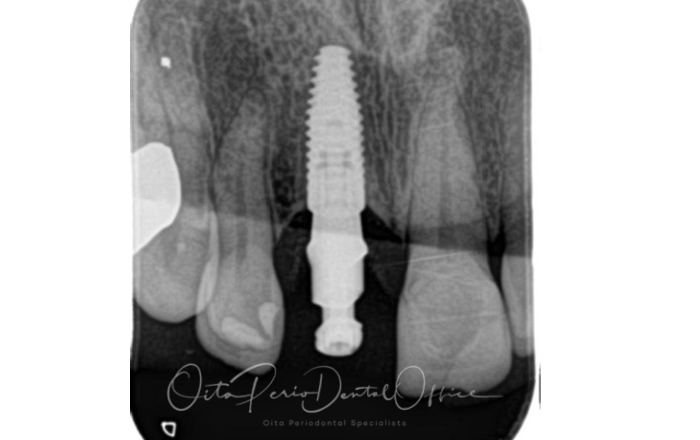

治療後のレントゲン